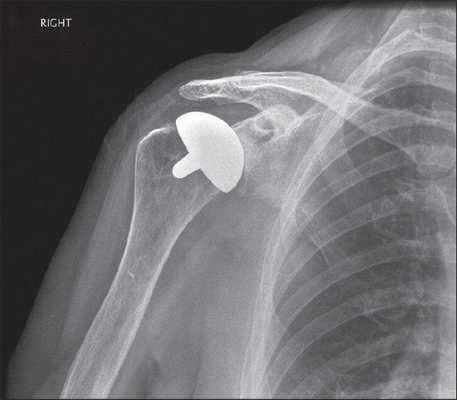

Плечевая гемиартропластика или поверхностное эндопротезирование плечевого сустава. Восстановление поверхности плечевой кости © Wikipedia

Гемиартропластика или поверхностное эндопротезирование плечевого сустава

При поверхностном эндопротезировании плечевого сустава замещается лишь поврежденная хрящевая поверхность плечевой головки. Кость плечевой головки при этом не удаляется. Такая модель протеза применяется в тех случаях, когда стабилизирующие мышцы плечевого сустава (вращающая манжета плеча) не повреждены или повреждены лишь незначительно, а плечевая впадина (гленоид) не имеет признаков износа. Благодаря такому типу протеза плечевой сустав восстанавливается при помощи установки металлической поверхности на плечевую головку на вершине плечевой кости. Хрящ на поверхности суставного углубления (гленоид) остается незатронутым. поверхностное эндопротезирование плечевого сустава позволяет сохранить неповрежденную или неизношенную поверхность сустава.

Одной из основных проблем при поверхностном эндопротезировании плечевого сустава является продолжающийся с течением времени износ поверхности суставного углубления. При преждевременном износе гленоидного компонента могут усиливаться болевые ощущения, а подвижность и несущая способность сустава снижаться.

После гемиартропластики плечевого сустава среднее улучшение амплитуды движения во всех направлениях составляет более 40°. Такой клинический результат схож с результатом после полного эндопротезирования плечевого сустава. Перед проведением поверхностного эндопротезирования специалист по плечевому суставу должен тщательно оценить поверхность суставной впадины и удостовериться в том, что она находится в достаточно хорошем состоянии, позволяющем достичь успешных результатов лечения.

При условии возможности проедения поверхностного эндопротезирования этот метод считается оптимальным методом лечения, поскольку он позволяет сохранить естественную поверхность кости и костное вещество плеча. При этом, если в будущем потребуется повторная операция, ее будет намного проще провести.